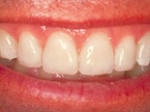

Före och efter behandling med fyra keramiska skalfasader.